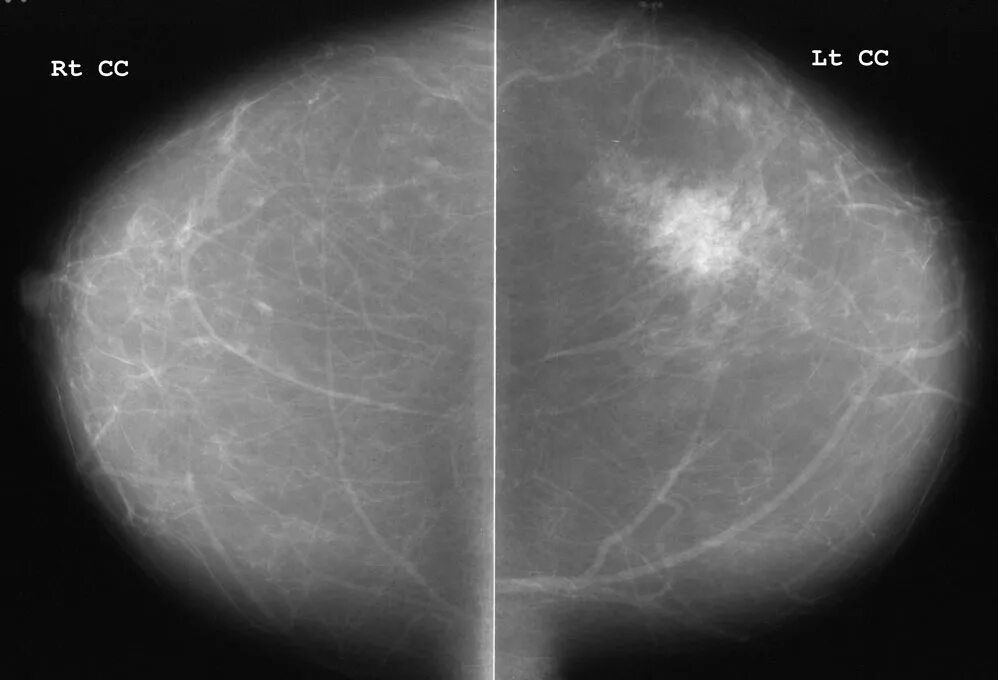

Диффузные доброкачественные